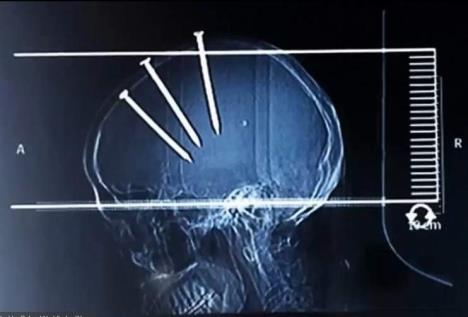

Jedan Kinez je čudom preživeo nakon što je sam sebi zakucao tri eksera dužine 10 centimetara.

Rendgenski snimak je pokazao da su ekseri prošli kroz njegovu lobanju i prodrli u mozak. Međutim, on je operisan u bolnici u okrugu Haifeng i potpuno se oporavio.